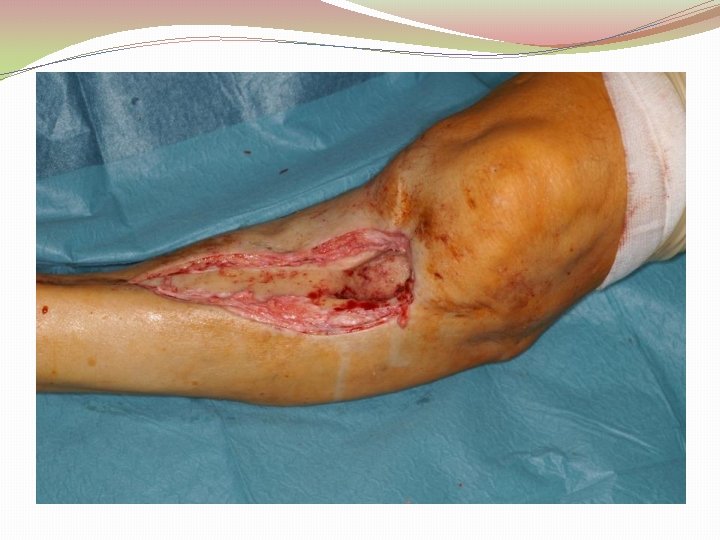

Ķirurģiska ārstēšana Osteomielīta pacientiem jāveic radikāls debridement ķirurģiski, kas ietver visu procesā iesaistīto audu rezekciju: �Mīksto audu rētas rezekcija �Cīpslu kalcinātu rezekcija �Distantu sekvestru rezekcija �Kaula rezekcija līdz vizuāli veseliem audiem – readzama punktveida asiņošana ´Paprika sign’. Bogdan Maciuceanu, Lucian Jiga, Alexandru Nistor, Jenel Marian Pastrascu, Mihail Ionac Chronic Osteomyelitis of Long Bones Timisoaral Medical Jornal, 2005

Ķirurģiska ārstēšana Veiksmīgas ķirurģiskas ārstēšanas stūrakmens ir mirušas telpas ‘Dead space’ aizpildīšana, kas izveidojas pēc debridemet veikšanas Brad Parsons, Elton Strauss, Surgical management of chronic osteomyelitis, The American Journal of Surgery 188 (Suppl to July 2004) 57 S– 66 S